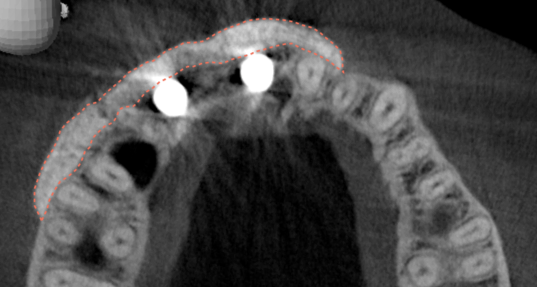

After the 3rd bone graft failed, the patient sought second opinions. She was a college sophomore at the time. Using a combination of interdisciplinary therapies, including S.M.A.R.T. minimally invasive bone grafting, Dr. Ernesto Lee was able to tridimensionally reconstruct this severe defect and place implants to restore the patient’s smile. The S.M.A.R.T. bone graft was also extended to treat adjacent teeth with thin/dehisced bone.

A long-term CAD/CAM fabricated temporary restoration is in place while she finishes medical school at an out-of-state university. The treatment of this case was published in detail in a special issue of the Compendium of Continuing Education in Dentistry, one of the largest circulation journals in our profession.